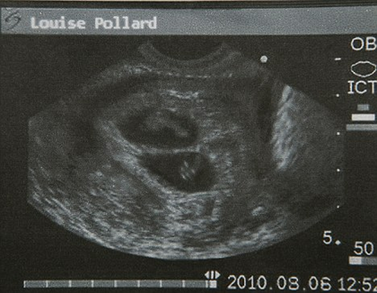

波拉德表示,她是本月6日在英國曼徹斯特一家私人診所做的超聲波檢查,影像資料顯示,她已經(jīng)成功受孕8周而且懷的是雙胞胎。自今年6月上旬波拉德公開承認(rèn)已答應(yīng)為奧馬爾夫婦代孕以來,她一直是英國媒體關(guān)注的焦點(diǎn)之一。

2010年8月6日,超聲波檢查顯示波拉德懷的是雙胞胎。